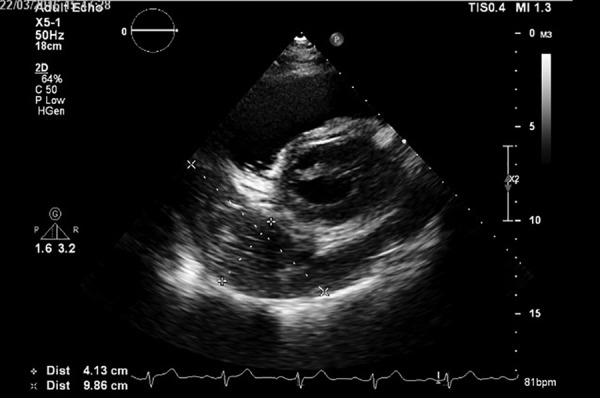

Sizing

• Measure between visceral and parietal pericardium at end diastole (multiple spots to increase accuracy to assess volume)

• Trivial (<10mm) <50mL

• seen only in systole

• Small (<10mm) 50-100mL

• Moderate (10-20mm) 100-500mL

• Large (>20mm) >500mL